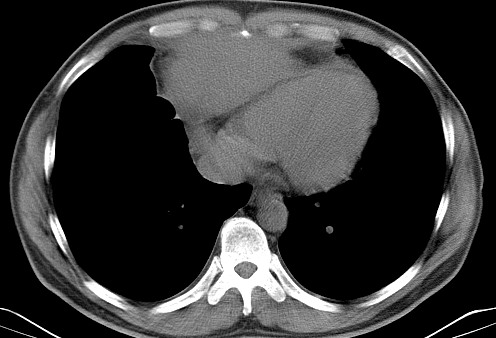

男   40   反复腹痛入院行彩超检查示胸骨右缘4、5肋间不均质回声团

淋巴瘤:前纵隔可见多组肿大的淋巴结,部分融合,有液化坏死

上区却那么有点象占位,胸腺瘤不太象,一点强化也没有,淋巴瘤气管前上腔静后却很干净,下区也点象纵隔积血征,